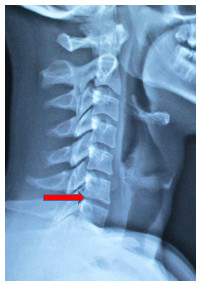

39歲的David是一位職業模特兒,今年2月因做舉重運動時扭傷了頸部,初時以為是肌肉發炎,但兩星期後仍然覺得頸部及手部痠軟無力、痺痛。接受了X光檢查,在X光片上沒有發現任何骨骼病變或椎孔收窄的情況,看起來應不是椎間盤突出的症狀,醫生便開了消炎止痛及鬆弛肌肉的藥物。初時服了藥物後是紓緩了一點,但相隔了兩個月後發現上手臂及右肩背肌肉有萎縮的跡象,而且在舉重時上手臂不能夠發力,感覺手軟、身體開始無力!筆者觀察他的肌肉萎縮情況並了解病歷後,認為應該是椎間盤突出的原因,由於X光片上只能看見頸椎第六、七節椎間輕微收窄了一些,而在照椎孔那張X光片上又看不見頸椎第六、七節有收窄的現象,相信單靠X光並不能夠為他確診出任何原因,後來筆者在診所內幫他做了磁力共振掃描,發現他頸椎第六、七節有一個頗大的椎間盤突出壓向右邊神經根,這處便是影響他右邊肩背、手部肌肉萎縮及右手無力的原因,而頸椎第五、六節間也有椎間盤突出,這便是造成他右手麻痺的因素。

X光片上只能看見案例一患者頸椎第六、七節椎

間輕微收窄了一些